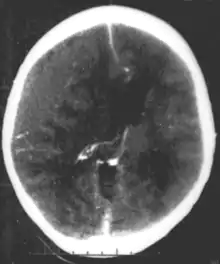

Hematoma epidural

O hematoma epidural acontece quando a hemorragia ocorre entre a membrana externa rígida que reveste o cérebro (dura-máter) e o crânio.[1] Muitas vezes, há perda de consciência após um traumatismo craniano, uma breve recuperação e, em seguida, uma nova perda de consciência.[2] Outros sintomas podem incluir cefaleia, confusão, náusea e paralisia.[3] Complicações podem incluir convulsões.[3]

A causa é tipicamente uma contusão na cabeça que resulta na fratura do osso temporal e hemorragia da artéria meníngea média.[1] Ocasionalmente, pode ocorrer devido a uma coagulopatia ou malformação vascular.[3] O diagnóstico geralmente é feito por tomografia computadorizada ou ressonância magnética.[3] Quando esta condição ocorre na coluna, é chamada de hematoma epidural espinhal.[1]